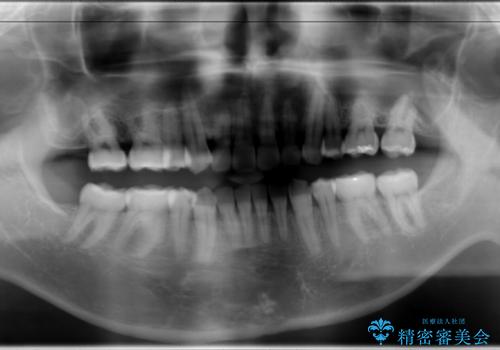

- 以前、上下左右4本抜いてワイヤー矯正をしていた方で、後戻りで下の前歯のガタガタを気にして来院されました。

マウスピース矯正にて、下の歯はIPR(歯と歯の間を削る)を入れることでガタガタの改善、咬み合わせの深さも改善をはかる治療計画をたてました。